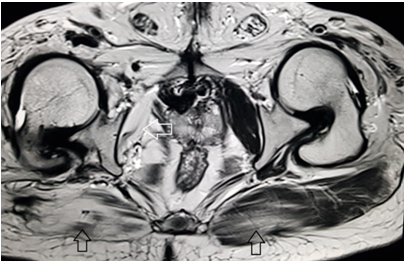

A 39 year old male presented with the chief complaint of pelvic discomfort and on and off haematuria. It was not associated with fever or urinary retention. No bowel symptoms were noted. Patient had history of paralytic poliomyelitis in his childhood and walked with crutches. On laboratory examination, patient was found to have deranged renal function tests with elevated creatinine level. Hence, we conducted MRI pelvis with MR urography to look for the urinary systemand to look for the status of the the pelvic muscles and joints. MR study showed multiple tortuous dilated vessels on the right side of pelvis suggestive of pelvic arteriovenous malformation (Figure 1&2). The arterial supply was noted from multiple branches of the right internal iliac artery and venous drainage was noted into right external iliac vein and deep external pudendal vein. The tangle of vessels was abutting the right lateral wall of urinary bladder, prostate and right seminal vesicle medially (Figure 1&3). It was abutting the obturatorinternus muscle laterally. There wasasymmetric thickening of the right lateral wall of urinary bladder adjacent to the vascular malformation (Figure 1). It was not associated with perivesicular fat strandings or enlarged locoregional lymphnodes. No restriction of diffusion was noted in DWI images. Prostate and bilateral bilateral seminal vesicles were normal in signal intensity and morphology. As a sequalae of childhood poliomyelitis, diffuse atrophy of pelvic muscles was noted that was more prominent on the right side (Figure 4&5). T1 and T2 high signal intensity suggestive of fatty replacement was noted in bilateral psoas and right obturaterinternus mucle. Fatty atrophy of bilateral hip and proximal thigh muscles were also seen (Figure 5). Abduction and external rotation was noted at bilateral hip joints (Figure 4). Histological examination of the bladder wall revealed polypoid bladder mucosa with chronic inflammation consistent with polypoid cystitis. Arteriovenous malformation was managed with intra-arterial coil embolization and subsequently the patient’s symptoms improved.

Figure 1 MRI axial T2 weighted image through the pelvis demonstrate multiple tortuous vessels (white arrow) on the right side extending to the right lateral wall of urinary bladder. The vessels are dilated and show loss of signal suggestive of high flow vascular malformation. Associated mild thickening of right lateral wall of urinary bladder is also noted (black arrow).